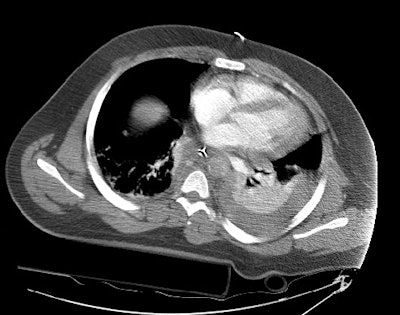

CT images more inferiorly revealed an intimal flap and marked irregularity to the contour of the aorta consistent with traumatic injury (black arrows). Slightly below this level there was a near complete lack of opacification of the vessel (lower image).

Images through the abdomen revealed a severely diminished aortic caliber and poor organ perfusion consistent with hypovolemic shock. The patient expired prior to angiography.